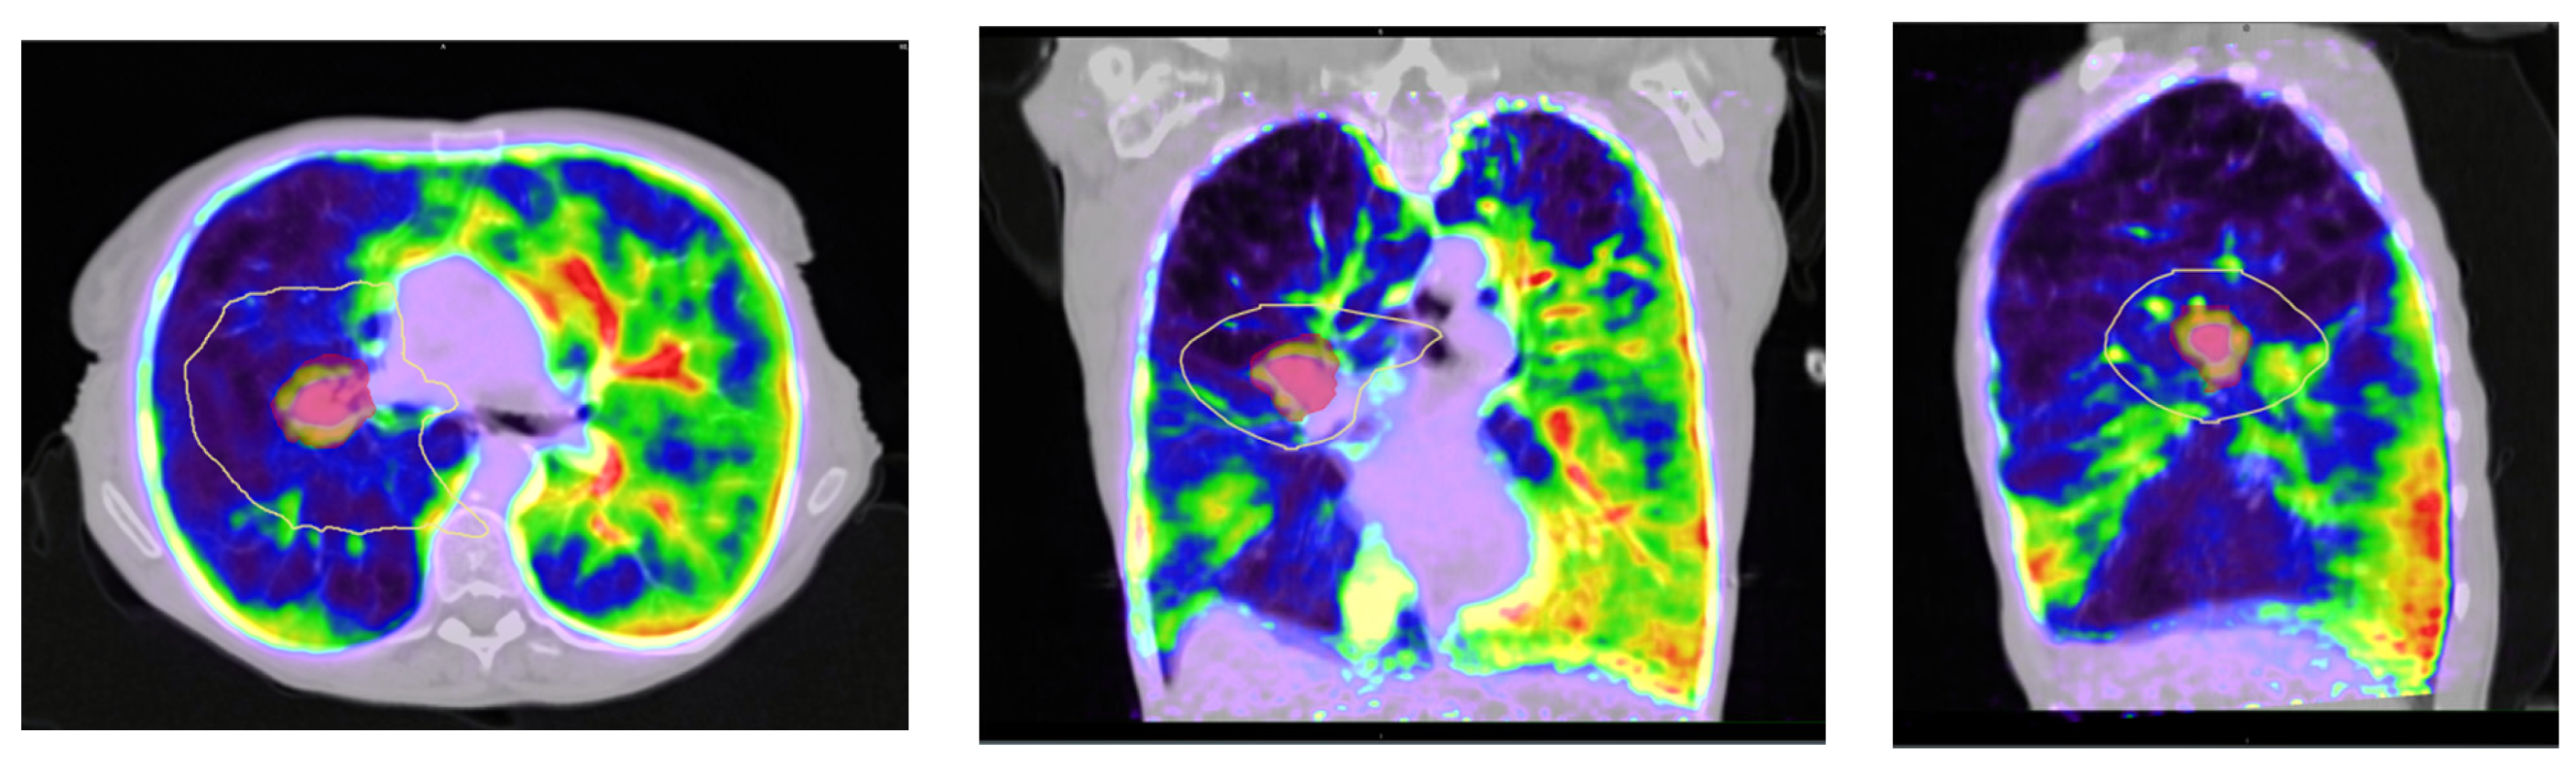

Lung Stereotactic Body Radiation Therapy in a Patient with Severe Lung Function Impairment Allowed by Gallium-68 Perfusion PET/CT Imaging: A Case Report

Lucia, F.; Hamya, M.; Pinot, F.; Bourhis, D.; Le Roux, P.-Y. Lung Stereotactic Body Radiation Therapy in a Patient with Severe Lung Function Impairment Allowed by Gallium-68 Perfusion PET/CT Imaging: A Case Report. Diagnostics 2023, 13, 718. https://doi.org/10.3390/diagnostics13040718